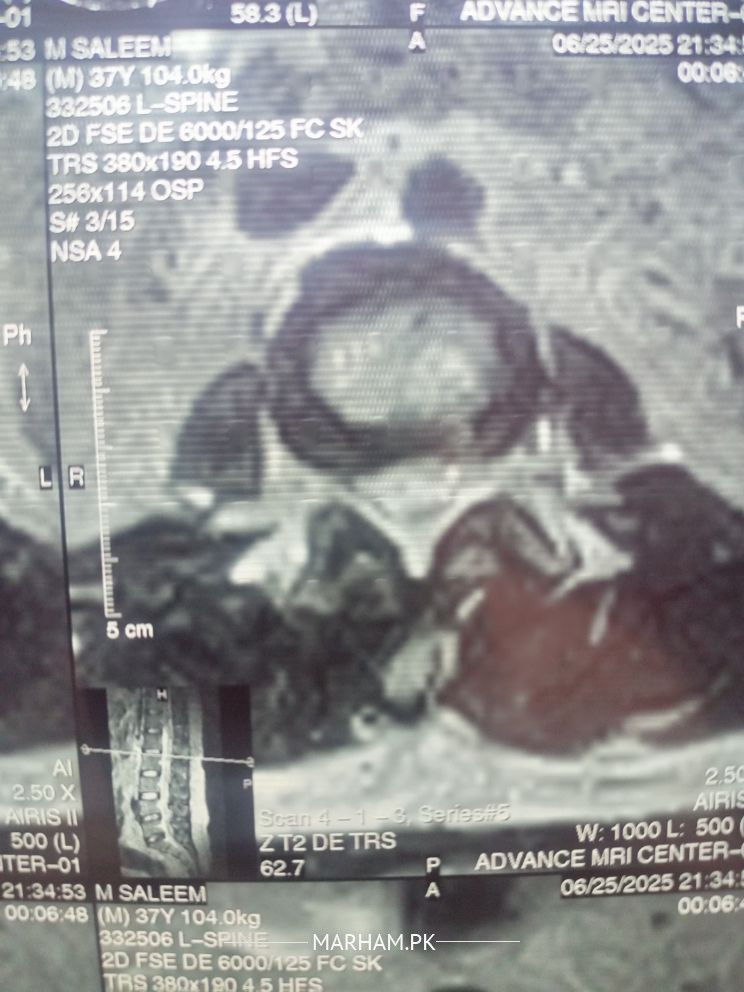

Physiotherapist in Lahore - Dr. Suleman Ashiq

your L4-L5 and L5-S1 discs are dehydrated, it can be due to some old cause, and L5-S1 is damaged more, may be due to improper lifting. so best solution is physiotherapy considering the complications of surgery, so yes physiotherapy will work if you give your therapist some time. good luck

It's not sciatica,It is disc dehydration at level L4-L5, but if you can share your MRI report that will be more helpful. yes physiotherapy will work for it but first visit a good orthopedic and then physiotherapis.